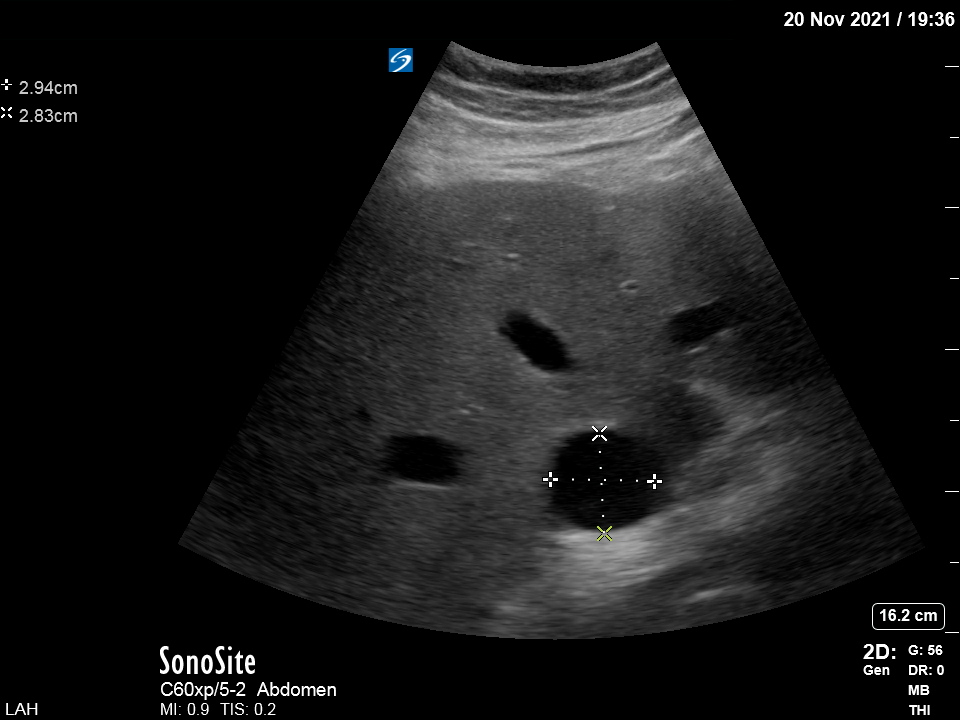

My next step was to look at the venous side. Pt tachypneic and in A fib (I will skip the poor HV and renal vein Doppler clips). This was the interesting transverse IVC view (at increased depth to look also at the R pleural space):

☝️Full IVC and large R effusion. The admission CXR was read as "no evidence of pleural effusion". This was the chest CT for comparison:

Back to the venous side and VEXUS. The IVC was large (almost 3 cm) but there were no "supportive" HV or renal vein Doppler images